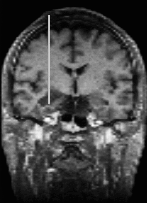

Figure 4:

Interventional MRI

Interventional MR systems allow for a continuous monitoring of the brain typically in a plane through the tip of the intervention device. Whereas a microscope can see only the immediate neighbourhood, interventional MR can look ahead and to the sides which gives more information and security for planning the next step. As the quality and the number of slices generated by an interventional MR is worse than with the preoperative MR, there is a need for registrating and fusing the current slices of the interventional MR with the high quality reference scene.